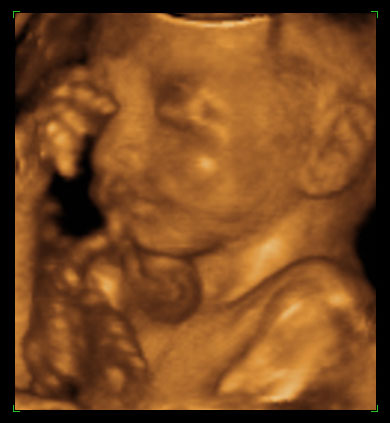

Dr Susan Robinson, who performs late term abortions

After Tiller: Meet the only four doctors in the U.S. who still perform third-trimester abortions despite constant threats to their lives” Mail Online Jan 21, 2013